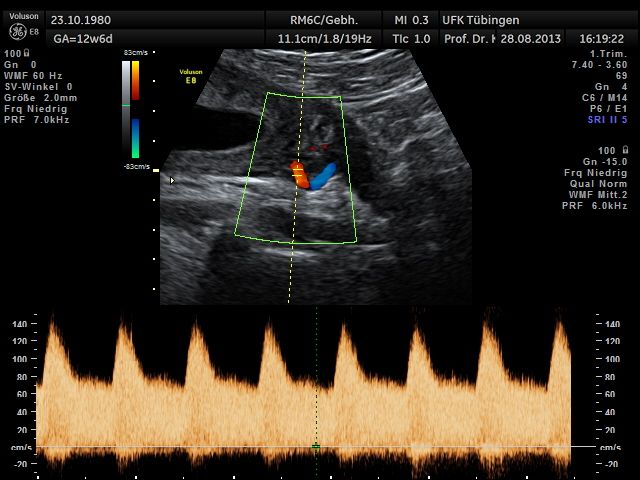

Herz

Das Ergebnis der Ultraschalluntersuchung ist wegweisend. Dabei wird der Fet vermessen, die Organe werden untersucht und die sonographischen Marker zur Risikoberechnung für Chromosomenstörungen werden beurteilt. Das sind: die Nackentransparenzdicke, Nasenbein sowie der Blutfluss in der rechten Herzhälfte und im Ductus venosus, einem Gefäß in der Leber des Feten.